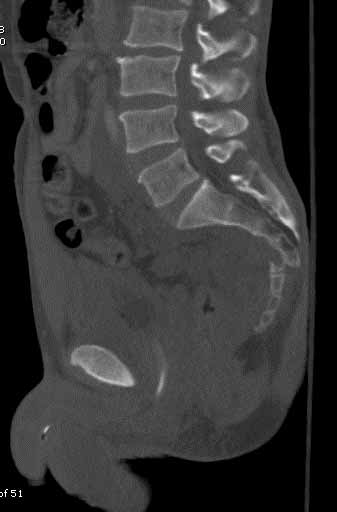

Subject: Low transverse sacral fracture

I have a patient who fell about 40 ft from a palm tree and survived. He sustained multiple orthopaedic injuries including comminuted subtroch., proximal humerus, and nondisplaced pelvic ring with zone 1 sacral fracture. The sacral fracture is well aligned but not impacted and will be stabilized with perc. Iliosacral screw. The anterior ring is nondisplaced. The patient also has this low transverse sacral fracture which is displaced. Would this low fracture benefit from ORIF or late excision if symptomatic? There is no discernable bowel or bladder neurologic injury.